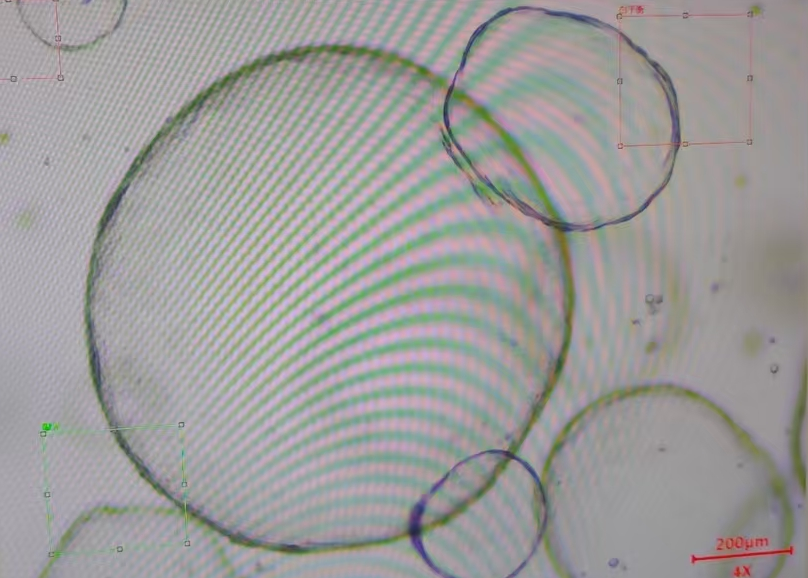

实践课由方博亲自教学,实验开始前,先让学员观察了不同类型样本的明场图,后续培养的时候可以更好的进行判断自己样本的培养情况。因为我们每种样本的取材及消化的判定都有所不同,所以本次特意展示了小鼠小肠、结肠、肺、肝、胃等多种样本。方博展示了类器官原代培养、传代培养、冻存的整个操作过程及注意事项。

小鼠肾组织原代消化图

小鼠小肠组织原代消化图

小鼠肺组织原代消化图

小鼠胃组织原代消化

人肝实质癌类器官

人胰腺癌类器官